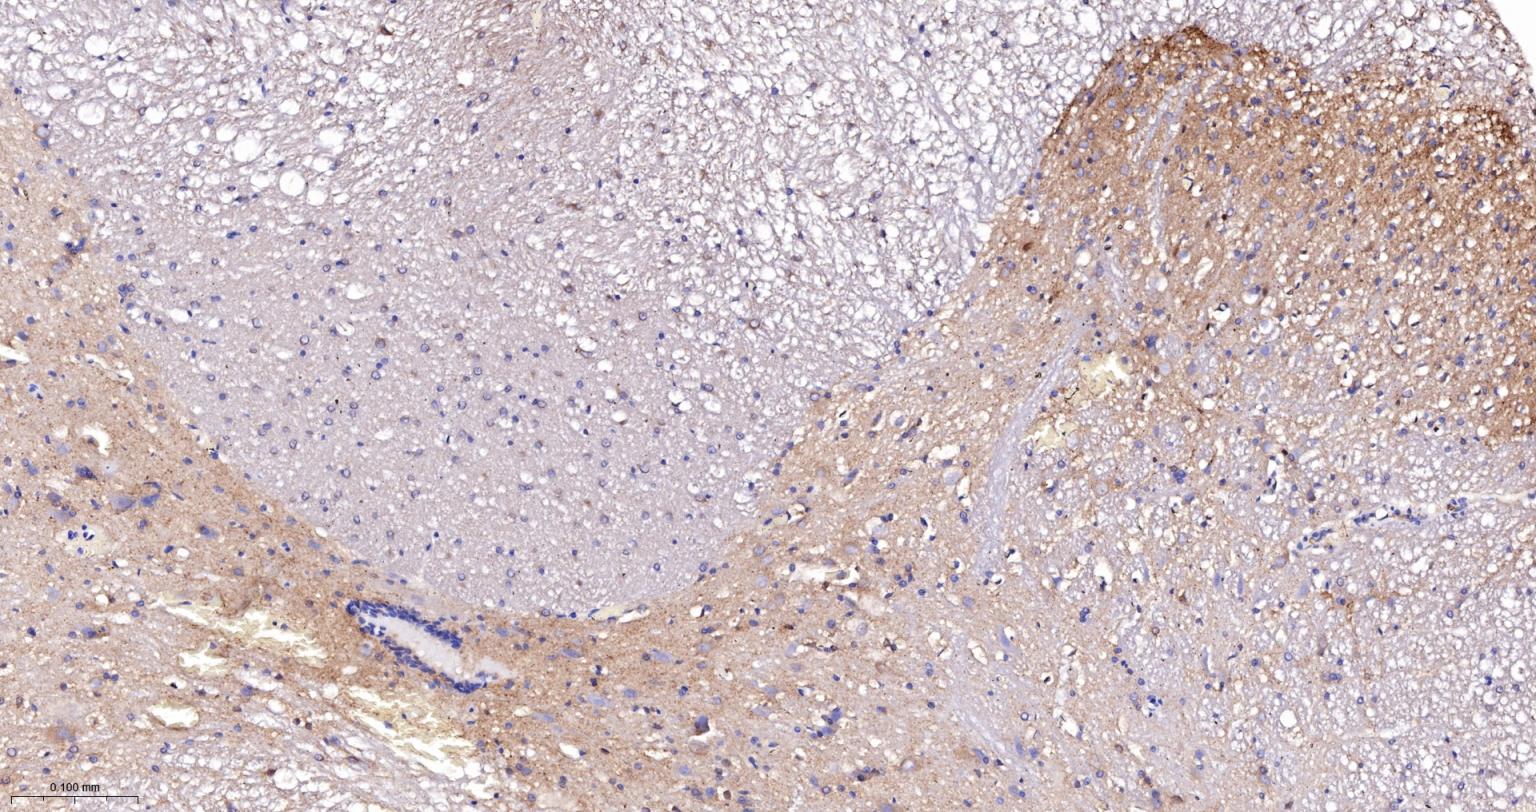

| IHC-P | Human, Mouse, Rat | 1:100-500 | |